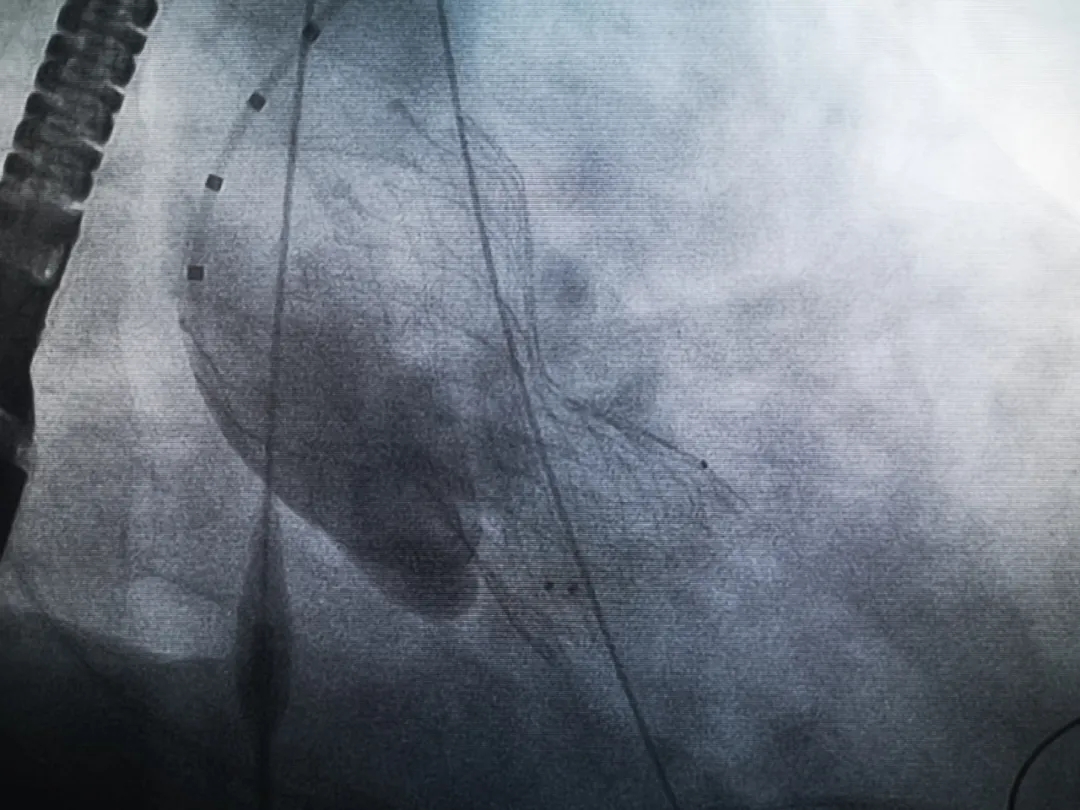

王子的手術被安排在周五。術前一天,TAVR團隊再次碰頭討論,從麻醉中血壓控制、球囊擴張、瓣膜釋放,到各種可能突發(fā)狀況的應對,都提前制定了方案。尤其是瓣膜鈣化極為嚴重,對于擴張球囊型號的選擇、擴張的力度以及瓣膜植入后瓣周漏的發(fā)生預測,都具有很大挑戰(zhàn)。然而,如果沒有這些挑戰(zhàn),他又何必選擇我們呢!

手術過程緊張而有序,心臟沒有停跳,也沒有太大的血壓波動;球囊擴張的恰到好處,瓣膜釋放之后超聲醫(yī)生的評估是至關重要的,因為我們提前就準備了后擴張,也準備了瓣中瓣,甚至還準備了瓣周漏封堵。所幸的是,超聲診療中心劉夢梅醫(yī)生說:沒有返流、沒有瓣周漏,瓣膜形態(tài)良好,跨瓣壓差約17mmHg(相較于術前的87mmHg還是可以接受的)。瓣膜置入的成功并不是慶祝的時候,從戰(zhàn)場撤退仍然需要謹慎。由于王子特別胖,腹股溝區(qū)脂肪尤為肥厚,在股動脈插管拔除、確認搏動正常之后,便逐層縫合。同時為了美觀、縫合之后不至于鼓個包出來,我們又仔細剪除了部分脂肪。術后次日,王子便可以下床活動了。